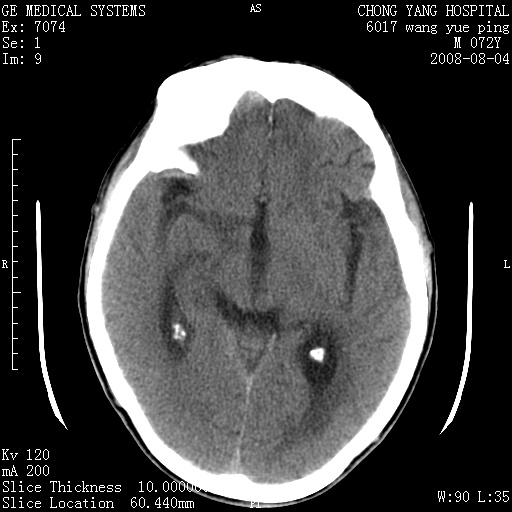

标题: CT14987:M72Y,头痛头昏,BP220/110. [打印本页]

标题: CT14987:M72Y,头痛头昏,BP220/110.

1)考虑左侧小脑脑梗塞。2)脑白质病。3)脑萎缩。4)双侧鼻腔新生物(息肉?)并阻塞性副鼻窦炎。

1.左侧小脑大面积梗塞;2.左侧基底节区腔梗;3.白质疏松;4.脑萎缩;5.慢性副鼻窦炎

小脑左侧病灶呈扇形分布,增强后未见明显瘤体样节结影,病变区未见强化。

支持:左侧小脑脑梗塞梗塞表现

另:脑白质病。脑萎缩。双侧鼻腔新生物(息肉?)并阻塞性副鼻窦炎。

1)考虑左侧小脑脑梗塞,建议治疗后复查除外其他,左基底节区腔隙性脑梗塞2)脑白质变性3)脑萎缩。4)双侧鼻腔新生物(息肉?)并阻塞性副鼻窦炎。